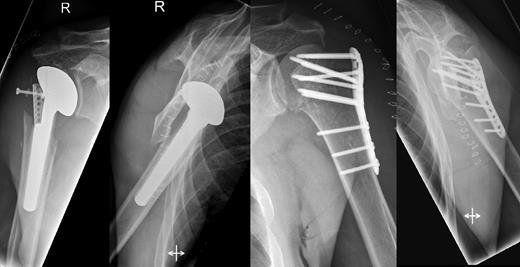

A 48-year-old patient was referred to a level I trauma center after the first incidence of an epileptic convulsion. The patient was alert and oriented with retrograde amnesia from the time of convulsion. Peripheral neurology was normal. The X-rays showed bilateral posterior shoulder dislocation with fractures of both humeral heads (Fig. 1). A CT of the head and both shoulders was performed to exclude intracerebral pathology and to achieve better demonstration of the shoulder fractures (Fig. 2). According to the AO fracture classification, he had a 11-C3.1 fracture on the left side and a 11-C3.3 fracture on the right side. The right side fracture was treated with a cementless hemiarthroplasty (OrTra®, Zimmer, Germany), while an open reduction and internal fixation (ORIF) with an angular stable plate (Philos®, Synthes, Germany) was performed on the left. Despite the high incidence for humeral head necrosis after ORIF in this fracture type, this option was chosen based on the young age of the patient. Postoperative X-rays and CT showed adequate positions of the implants (Fig. 3). The shoulders were immobilized in Gilchrist bandages followed by passive mobilization for the first 6 weeks by physiotherapy with a limitation for abduction and anteversion to 90°. There were no complications intraoperatively or in the first postoperative time. Patient was discharged after 8 days. Antiepileptic therapy was initiated with 5 mg clobazam and subsequent increasing doses over the following weeks. There were no more signs of epilepsy in the follow-up. A CT 4 months after operation showed dislocation of a fragment on the left side which was subsequently resected. At the 1-year postoperative review, the patient showed impingement of the left shoulder with abduction limited to 50° by both the plate and an osteophyte. Radiological assessment revealed signs of necrosis of the head. The plate was removed and the osteophyte resected. Eighteen months after injury, the left shoulder showed progressive avascular osetonecrosis of the head (Fig. 4) and after plate removal an inversed prosthetic replacement had to be performed (Fig. 5). At the last follow-up 3 years after injury, the patient was free of pain with a bilateral range of motion of 90° abduction and elevation.

Postoperative X-rays after hemiprothetic replacement on the right and angle stable plate osteosynthesis on the left side.